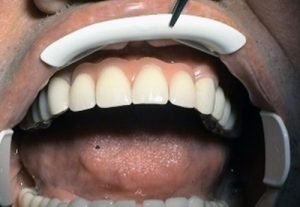

Prosthetic treatment in a toothless jawbone carried - 5 implants

1. PHASE - implant placement

2. PHASE - state before the provisional solution was made

3. PHASE - making a temporary solution

4.PHASE - implant placement